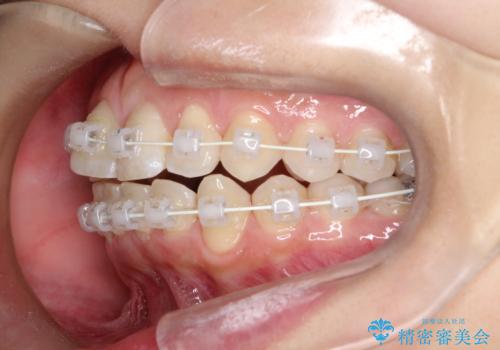

右下第二小臼歯の舌側転移の改善

- 矯正装置

- 患者様は、右下第二小臼歯が舌側に転移していることが主訴でした。診断の結果、抜歯を伴う矯正治療も検討しましたが、奥歯の遠心移動とIPR(インタープロキシマルリダクション)を行うことで、非抜歯で矯正を進めることが可能であると判断しました。治療計画では、審美ワイヤーを用いた2年間の治療で、歯列を整えつつ、臼歯関係や正中のバランスを維持しながら進めました。

非抜歯矯正では、歯の動きを慎重に調整することが求められます。本症例では、奥歯を遠心に移動させることで、舌側に転移した右下第二小臼歯の位置を改善しました。また、IPRを行うことで歯間スペースを確保し、無理なく歯列の調整を行いました。非抜歯での治療は、特に臼歯関係や正中を保ちながら治療できるというメリットがあり、最終的にはバランスの取れた歯並びを実現できました。審美ワイヤーを使用したことで、治療中も目立ちにくく、患者様の見た目にも配慮した治療を行いました。